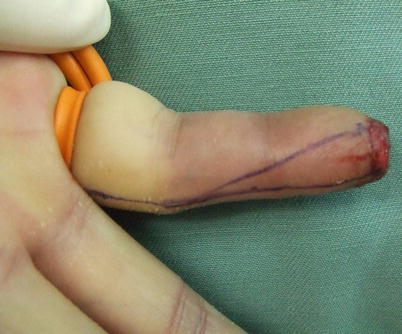

Fig. 8.2

Procedure 2: First, a line is drawn along the full length of the mid-lateral line of the finger, and the width of the distal end of the flap is decided by the longitudinal diameter of the finger amputation stump. From that point a line is drawn diagonally to the PIP joint, and a long narrow flap is designed

Fig. 8.3

Procedure 3: An incision is made in the margin of the flap. A deep incision is made in the line along the mid-lateral line of the finger down to the periosteum, and a shallow incision is made subcutaneously along the diagonal line